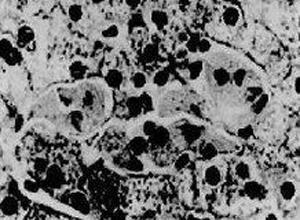

简介岩藻糖苷贮积症(fucosidosis)是一种因α岩藻糖苷酶缺陷而引起的类黏多糖贮积症,临床上以神经系统异常、反复呼吸道感染、智力低下及心脏病变为特征,无黏多糖尿。